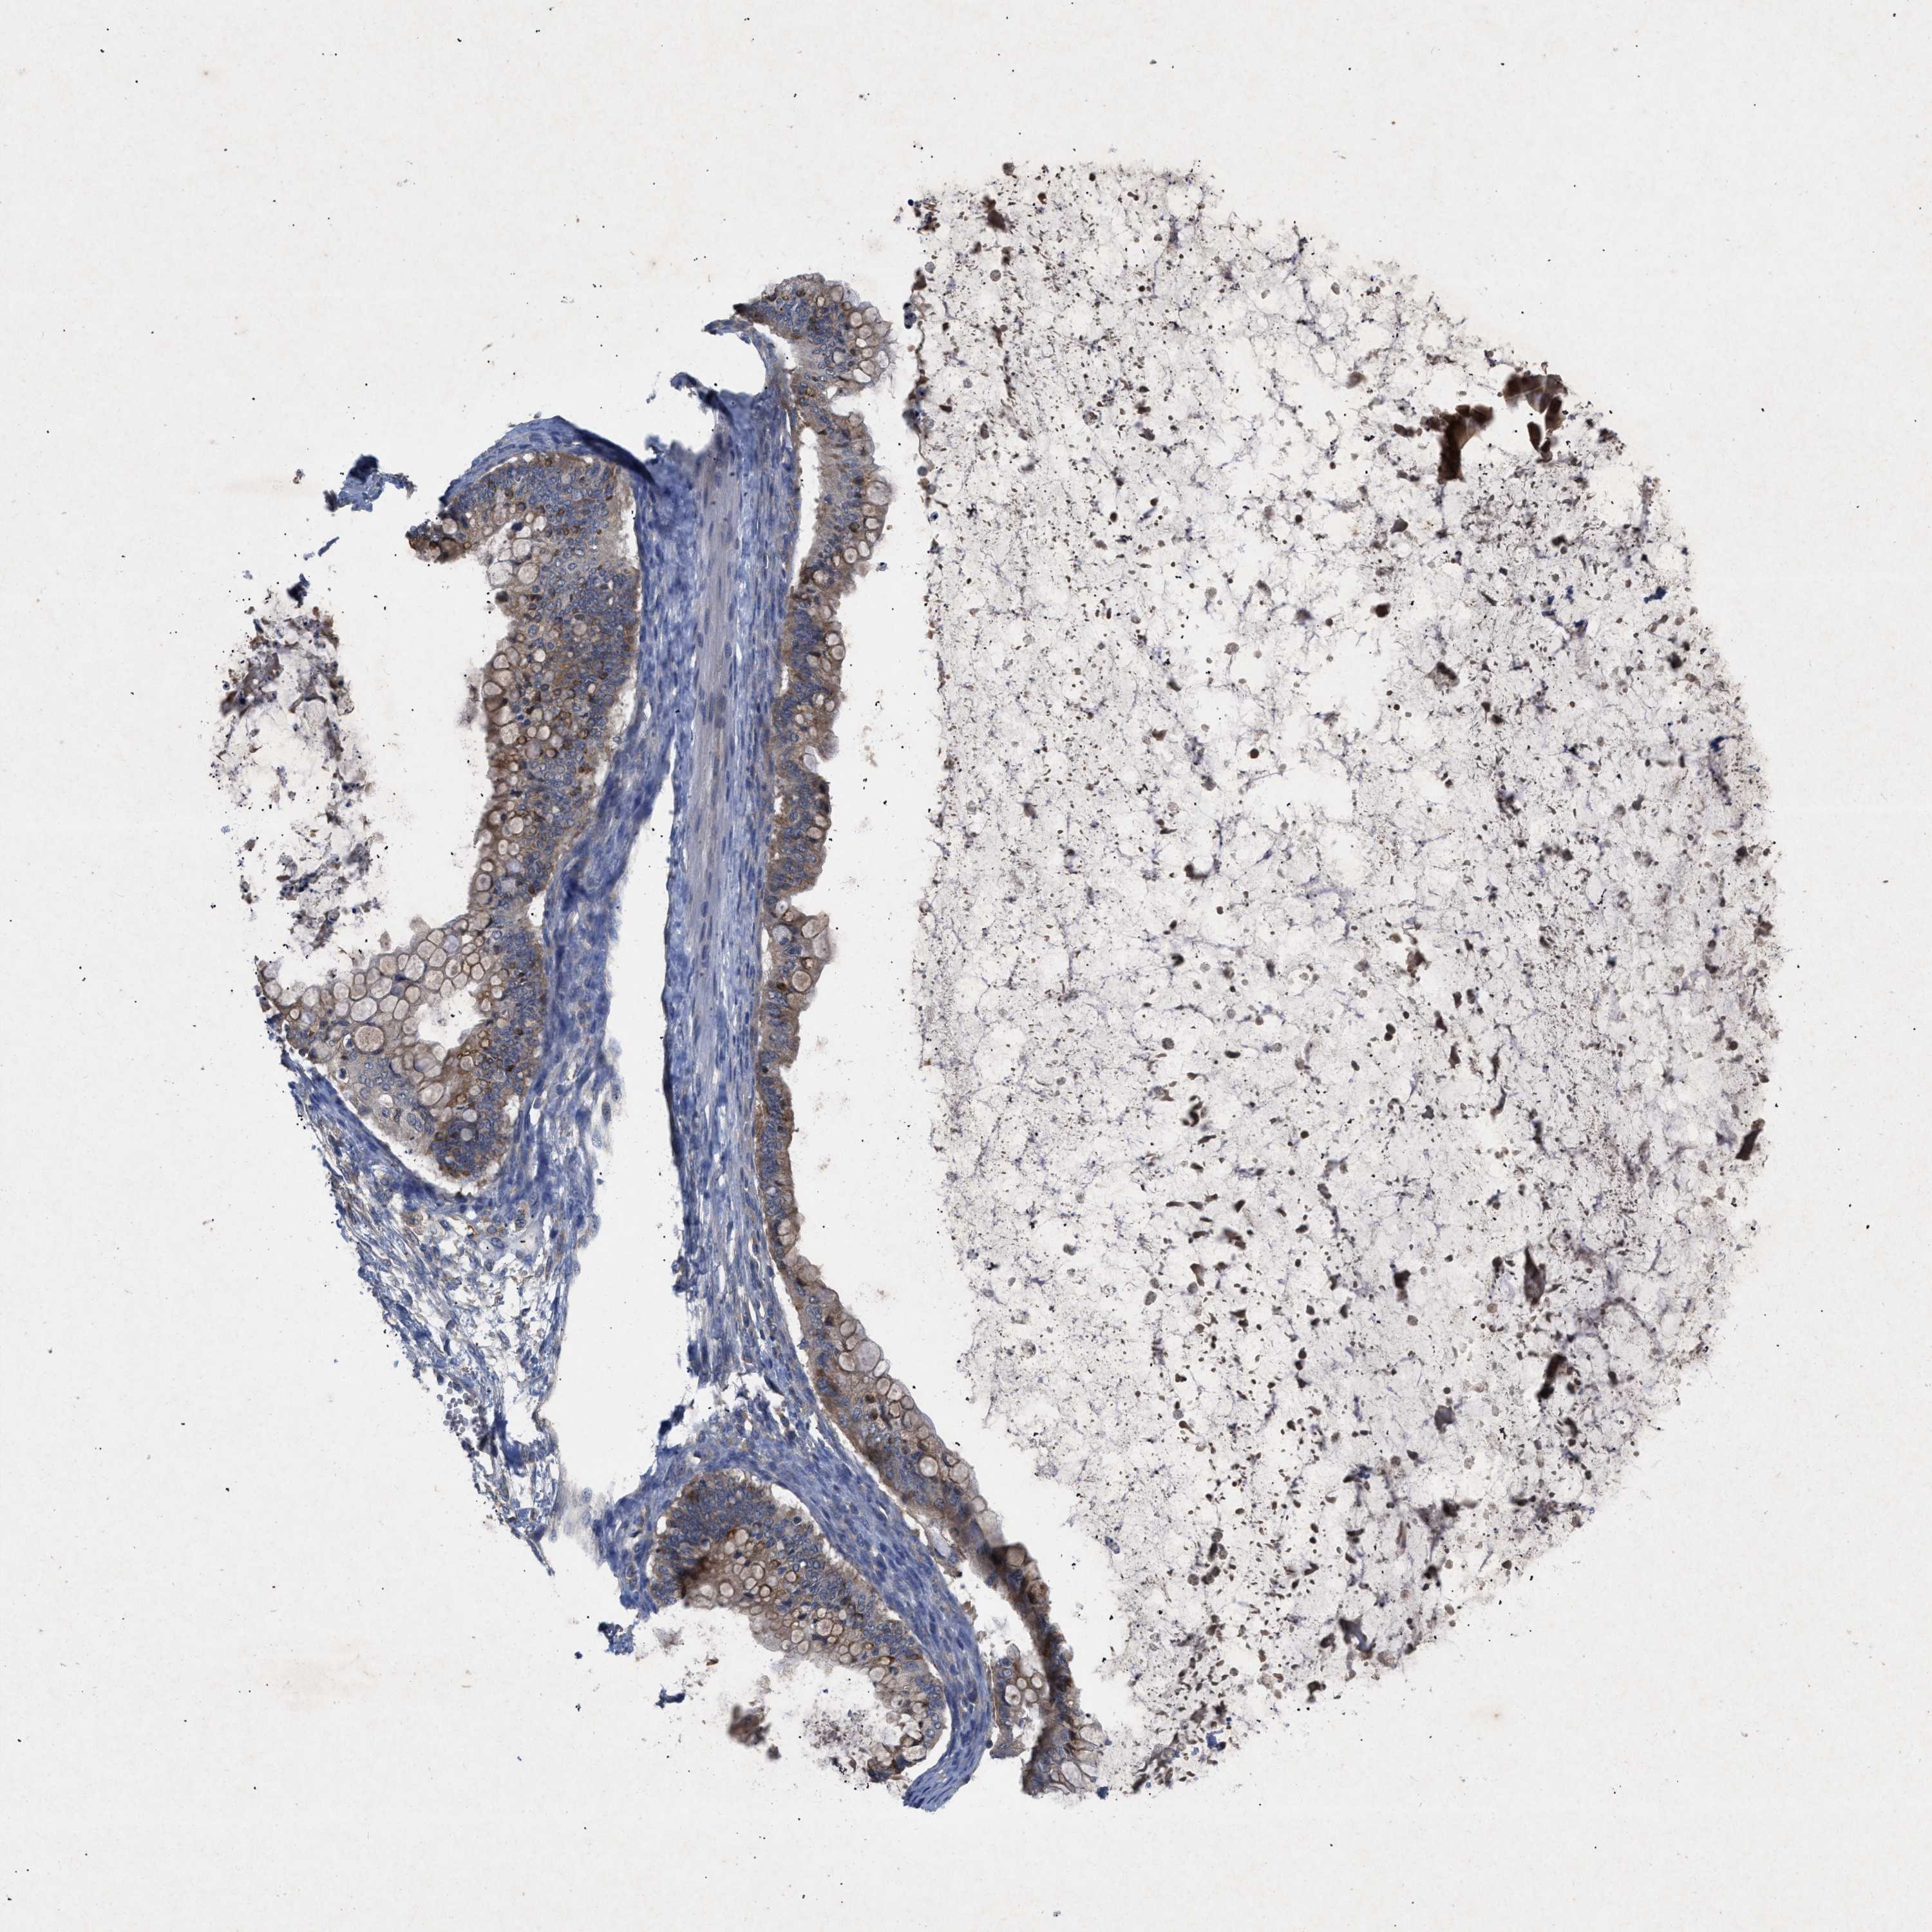

OVARIAN CANCER - Protein expressioni

A mouse-over function shows sample information and annotation data. Click on an image to view it in a full screen mode. Samples can be filtered based on level of antibody staining by selecting one or several of the following categories: high, medium, low and not detected. The assay and annotation is described here.

Note that samples used for immunohistochemistry by the Human Protein Atlas do not correspond to samples in the TCGA dataset.

Antibody stainingi

Antibody staining in the annotated cell types in the current human tissue is reported as not detected, low, medium, or high, based on conventional immunohistochemistry profiling in selected tissues. This score is based on the combination of the staining intensity and fraction of stained cells.

Each image is clickable and will lead to virtual microscopy that enables deeper exploration of all samples and also displays staining intensity scores, fraction scores and subcellular localization as well as patient and tissue information for each sample.

Antibody CAB018751

Antibody CAB034411

Cystadenocarcinoma, serous, NOS

Carcinoma, endometroid

Cystadenocarcinoma, mucinous, NOS

Carcinoma, NOS